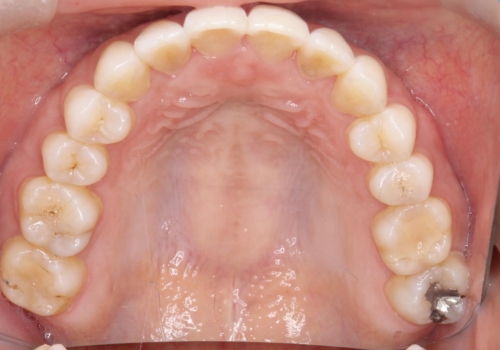

【インビザライン】前歯の凸凹をなおしたい

- 前歯の凸凹を主訴に来院されました。

上顎の急速拡大を行なったのちインビザラインにて治療を行なっております。

今回のケースは後戻りのリスクを低くし、またディスキング量を減らすために上顎の急速拡大を行なっております。